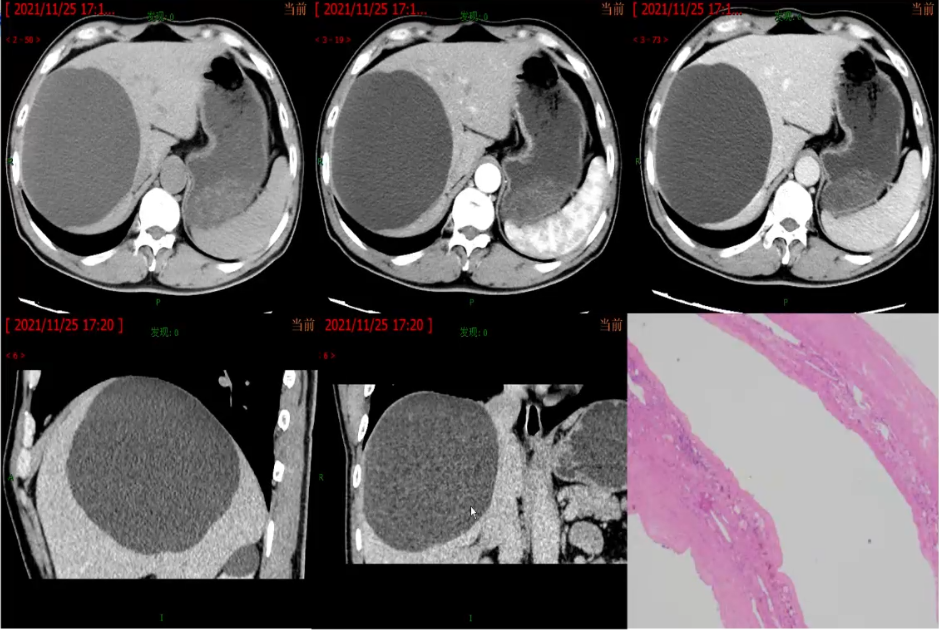

影像学表现:单发或多发、圆形、边界光滑锐利

CT:低密度影(CT值与水接近),增强扫描无强化

单纯性肝囊肿壁薄而光滑的病变,内衬立方上皮,分泌胆汁样液体,囊肿的直径<30 cm,并且可能包含多达2个隔膜